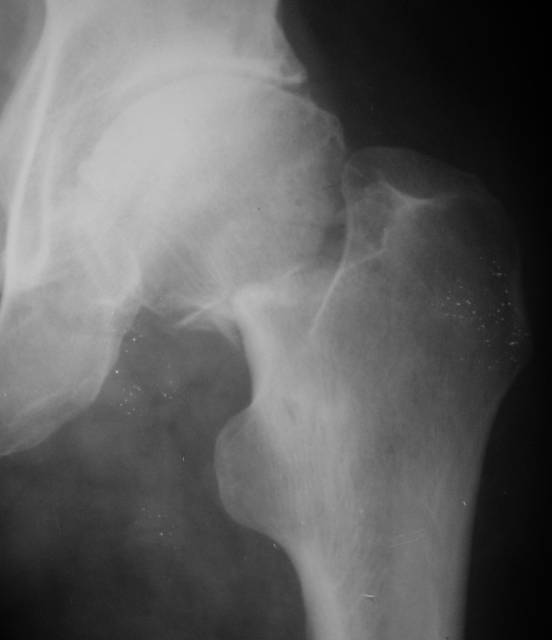

Еще пара фото, ситуация несколько иная, задачи те же, открытое вправление застарелого вывиха в 2002, молодой возраст. Сейчас госпитализирована для эндопротезирования.

Насчет 8 см согласен с А.Н. Челноковым, это наверное ортопедическое за счет приводящей, сгибательной контрактуры и, возможно, колена. на ликвидацию укорочения у нас обычно уходит около 2-х нед. снимки в приложении, возможно не очень показательные, но других с ходу не нашел, завтра еще поищу.